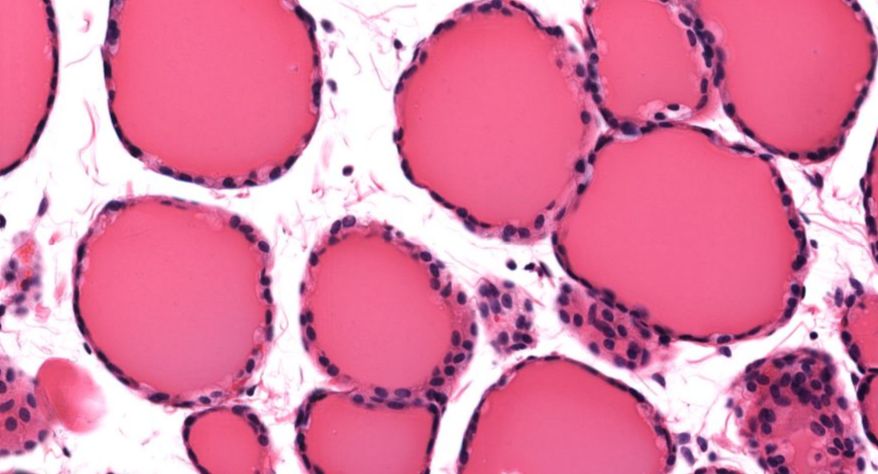

甲状腺

2.滤泡